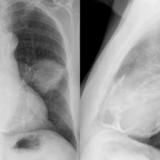

Part'l absc peric cu

Date: 07/23/2006

Views: 2423